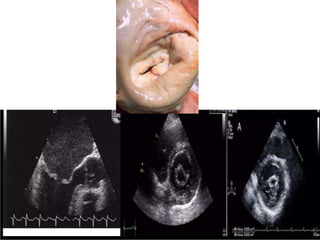

A)Long axis view-both leaflets are thickend with pliable anterior

leaflet

B)Short axis view-fusion of both commissures

C) A coptation defect of mitral can be detected with severely

dilated LA. D) colour flow mapping showing severe MR